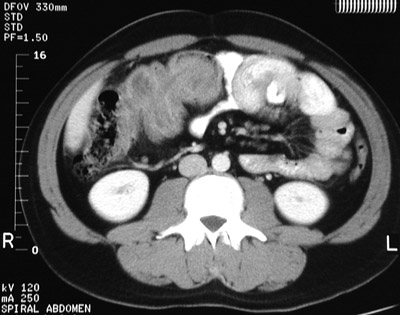

| There is an intussusception in the proximal part of the transverse colon in this abdominal CT scan. In the view below, the rounded leading mass, an adenocarcinoma, that led to this event can be seen. Of course, colonic intussusception, though rare, is much more likely to be an idiopathic event involving the ileocecal region of an infant. In adults, intralumenal masses may be caught by peristaltic waves and initiate intussusception. |